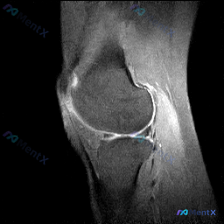

这是一例膝关节MRI T2序列矢状位影像,送检原因是怀疑存在半月板异常,系统评估各结构如下:

- 骨骼关节软骨:股骨远端、胫骨近端、髌骨轮廓正常,股骨滑车和胫骨平台关节软骨大致平滑,无明显全层缺损

- 半月板:本次可见的矢状位切面上,半月板呈典型楔形低信号,轮廓清晰,没有看到内部高信号延伸到关节面,不符合半月板撕裂或显著退变的表现

- 韧带肌腱:后交叉韧带走行自然、信号均匀连续,前交叉韧带走行可辨;髌腱和股四头肌腱形态都正常

- 关节内:没有明显病理性大量积液

- 关键异常发现:髌骨前方皮下区域,可见一片不规则局限性T2高信号,边界有炎症浸润特征,周围软组织伴随弥漫性水肿信号;膝关节深部结构(半月板、韧带、骨髓)都没有异常高信号